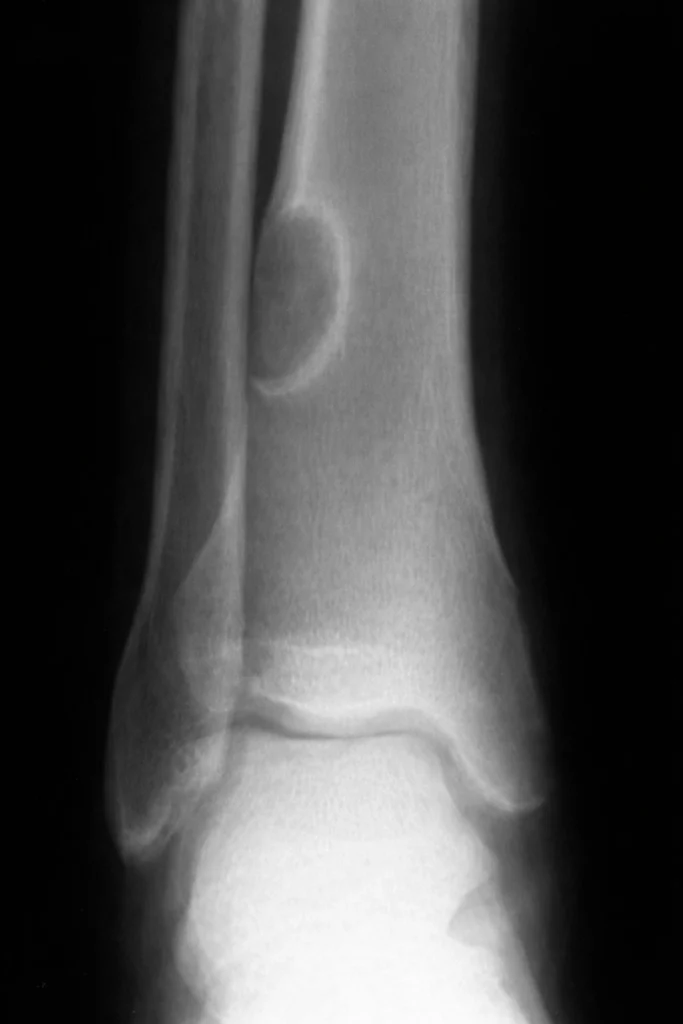

A nem osszifikálódó csontfibroma legtöbbször röntgen alapján felismerhető, mert jellegzetes képet ad: jól körülhatárolt, a csont külső részéhez közelebb elhelyezkedő, ritkább szerkezetű terület, gyakran vékony, fehéres szegéllyel. Emiatt sok esetben biopszia nem szükséges. Ha a kép nem típusos, a lézió nagy, vagy a csont stabilitása kérdéses, MRI vagy CT jöhet szóba.

A nem osszifikálódó csontfibroma (nonossifying fibroma, NOF) rostos szövetből álló, jóindulatú csontelváltozás. Nem rosszindulatú daganat, nem ad áttétet, és nem „terjed” a szervezetben. Leggyakrabban a hosszú csöves csontok csontvéghez közeli részén (metafízis) alakul ki – tipikusan a térd környékén (combcsont alsó, sípcsont felső/alsó szakasz).